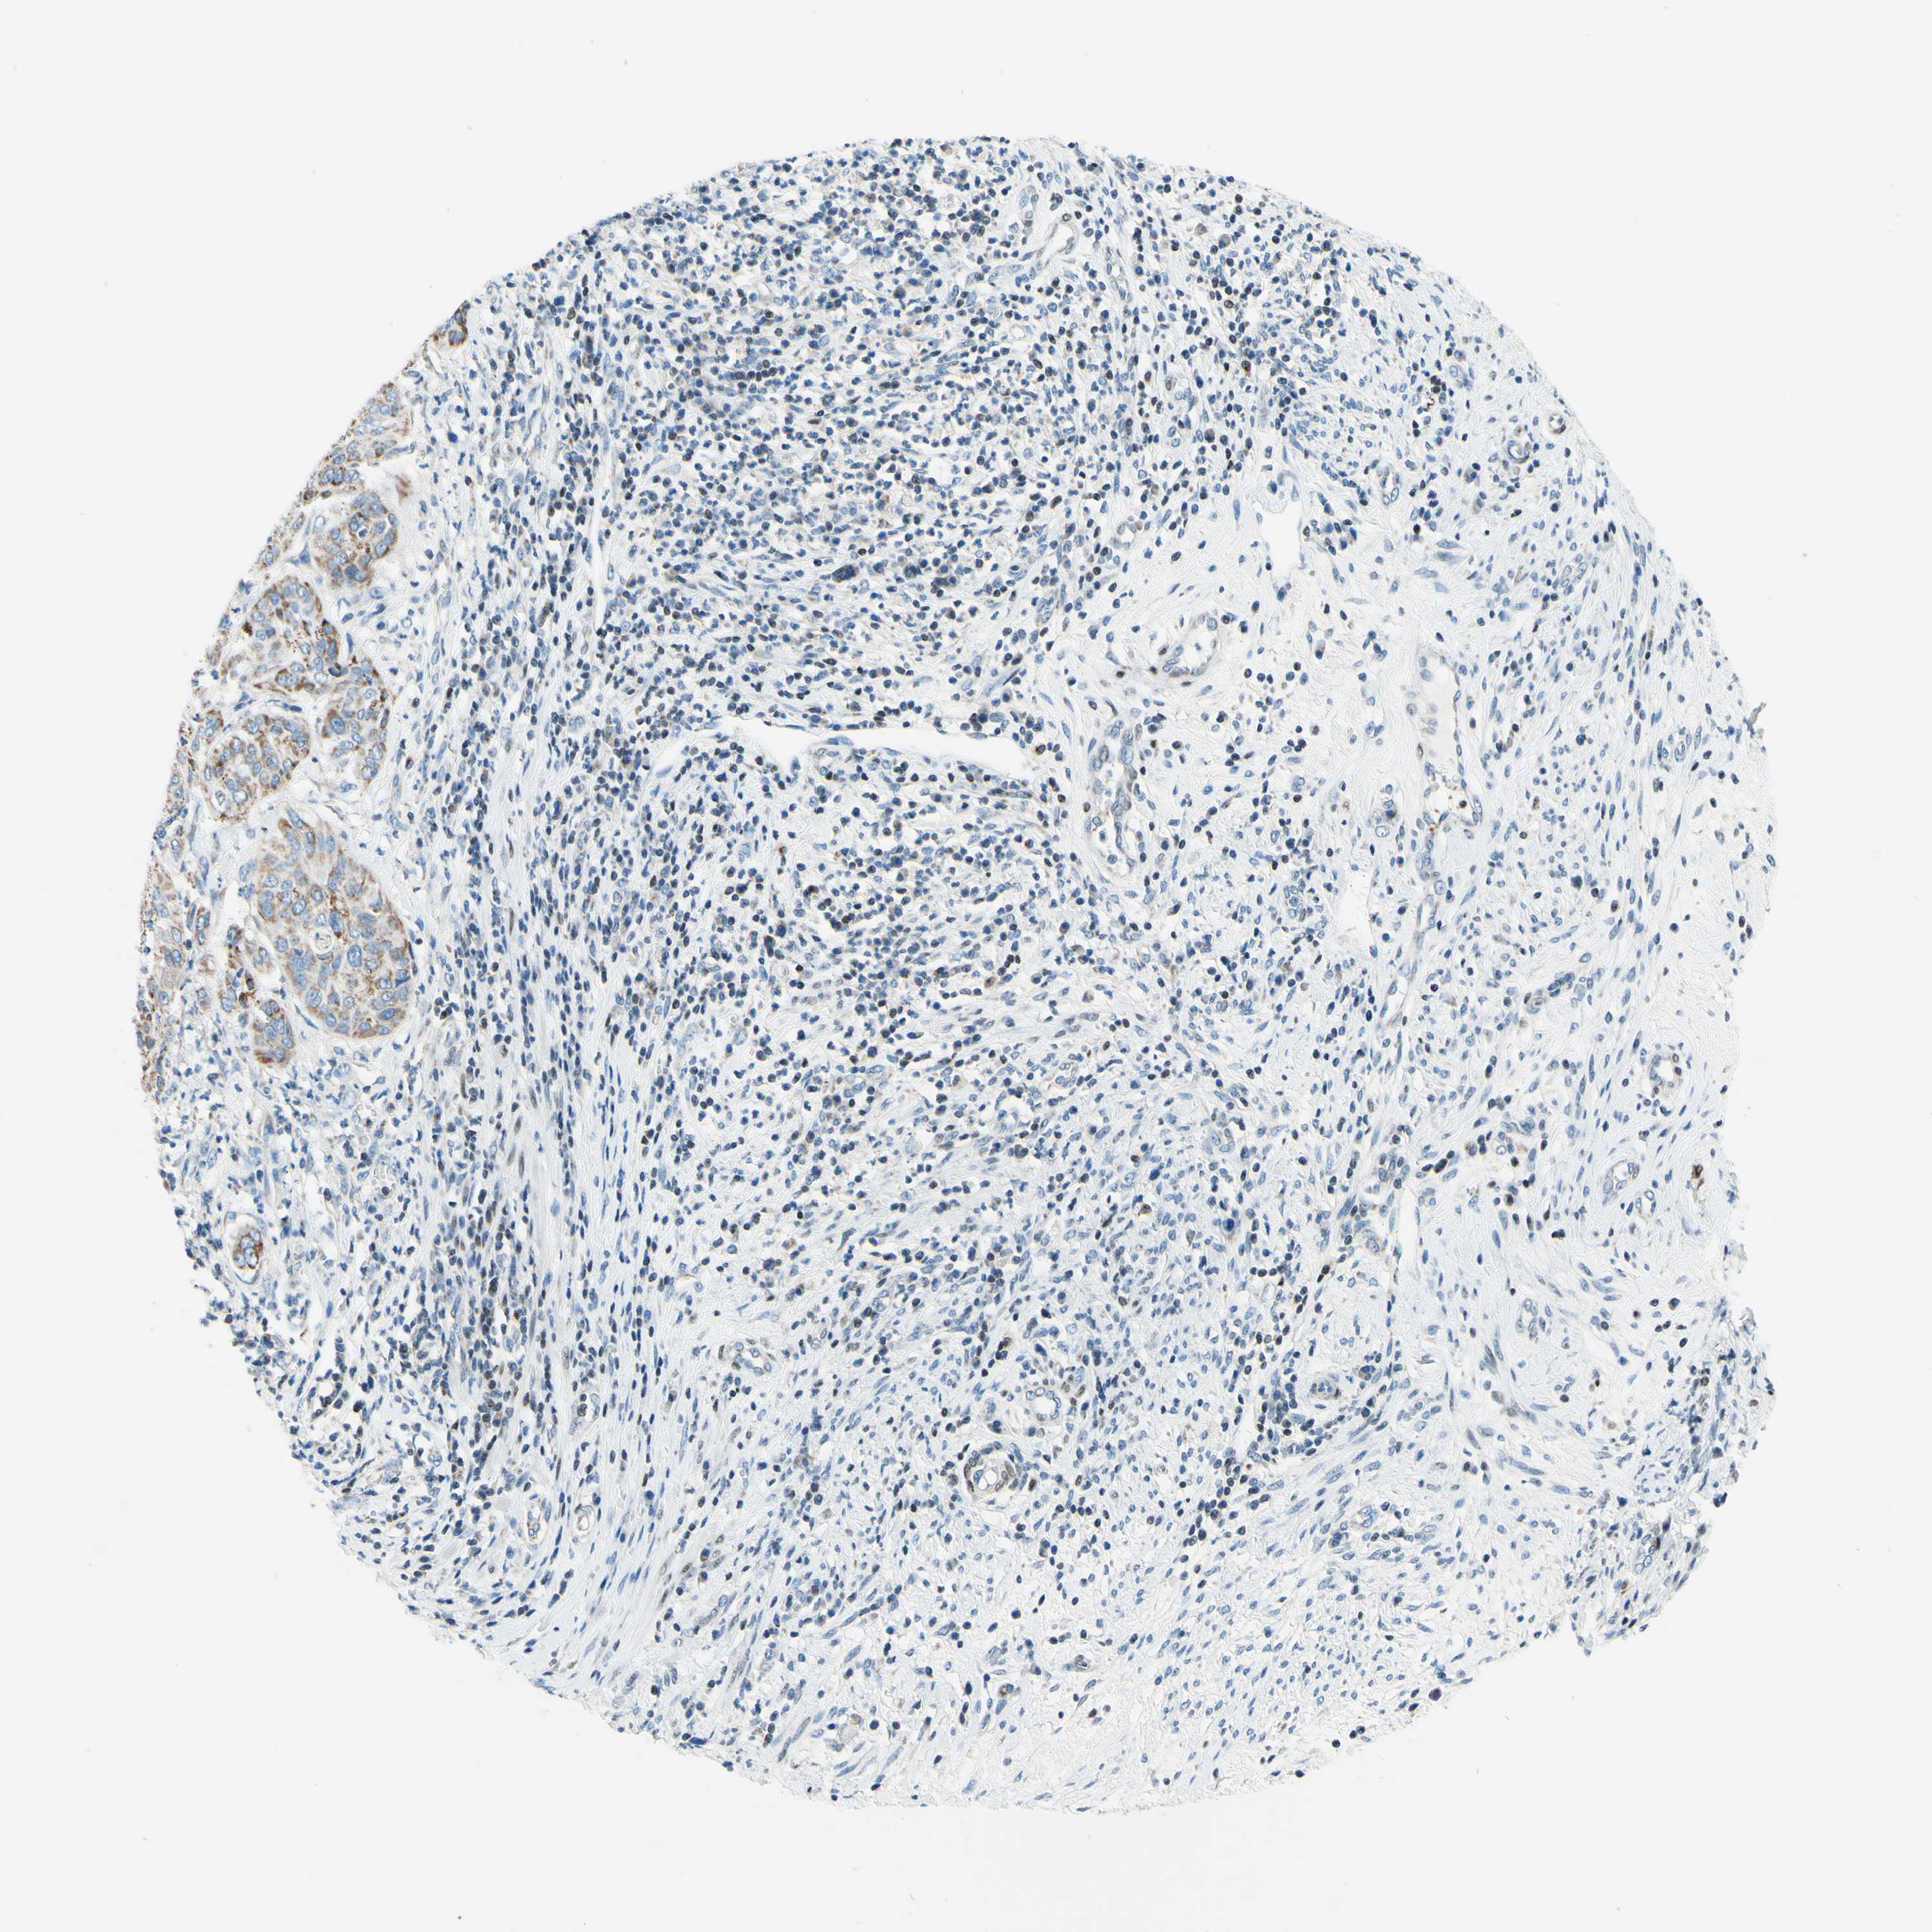

CERVICAL CANCER - Protein expressioni

A mouse-over function shows sample information and annotation data. Click on an image to view it in a full screen mode. Samples can be filtered based on level of antibody staining by selecting one or several of the following categories: high, medium, low and not detected. The assay and annotation is described here.

Note that samples used for immunohistochemistry by the Human Protein Atlas do not correspond to samples in the TCGA dataset.

Antibody stainingi

Antibody staining in the annotated cell types in the current human tissue is reported as not detected, low, medium, or high, based on conventional immunohistochemistry profiling in selected tissues. This score is based on the combination of the staining intensity and fraction of stained cells.

Each image is clickable and will lead to virtual microscopy that enables deeper exploration of all samples and also displays staining intensity scores, fraction scores and subcellular localization as well as patient and tissue information for each sample.

Antibody HPA048677

Antibody HPA056480

Antibody CAB011574

Staining

High

Medium

Low

Not detected

Intensity

Strong

Moderate

Weak

Negative

Quantity

>75%

75%-25%

<25%

None

Location

Nuclear

Cytoplasmic/membranous

Cytoplasmic/membranous,nuclear

Adenocarcinoma, NOS